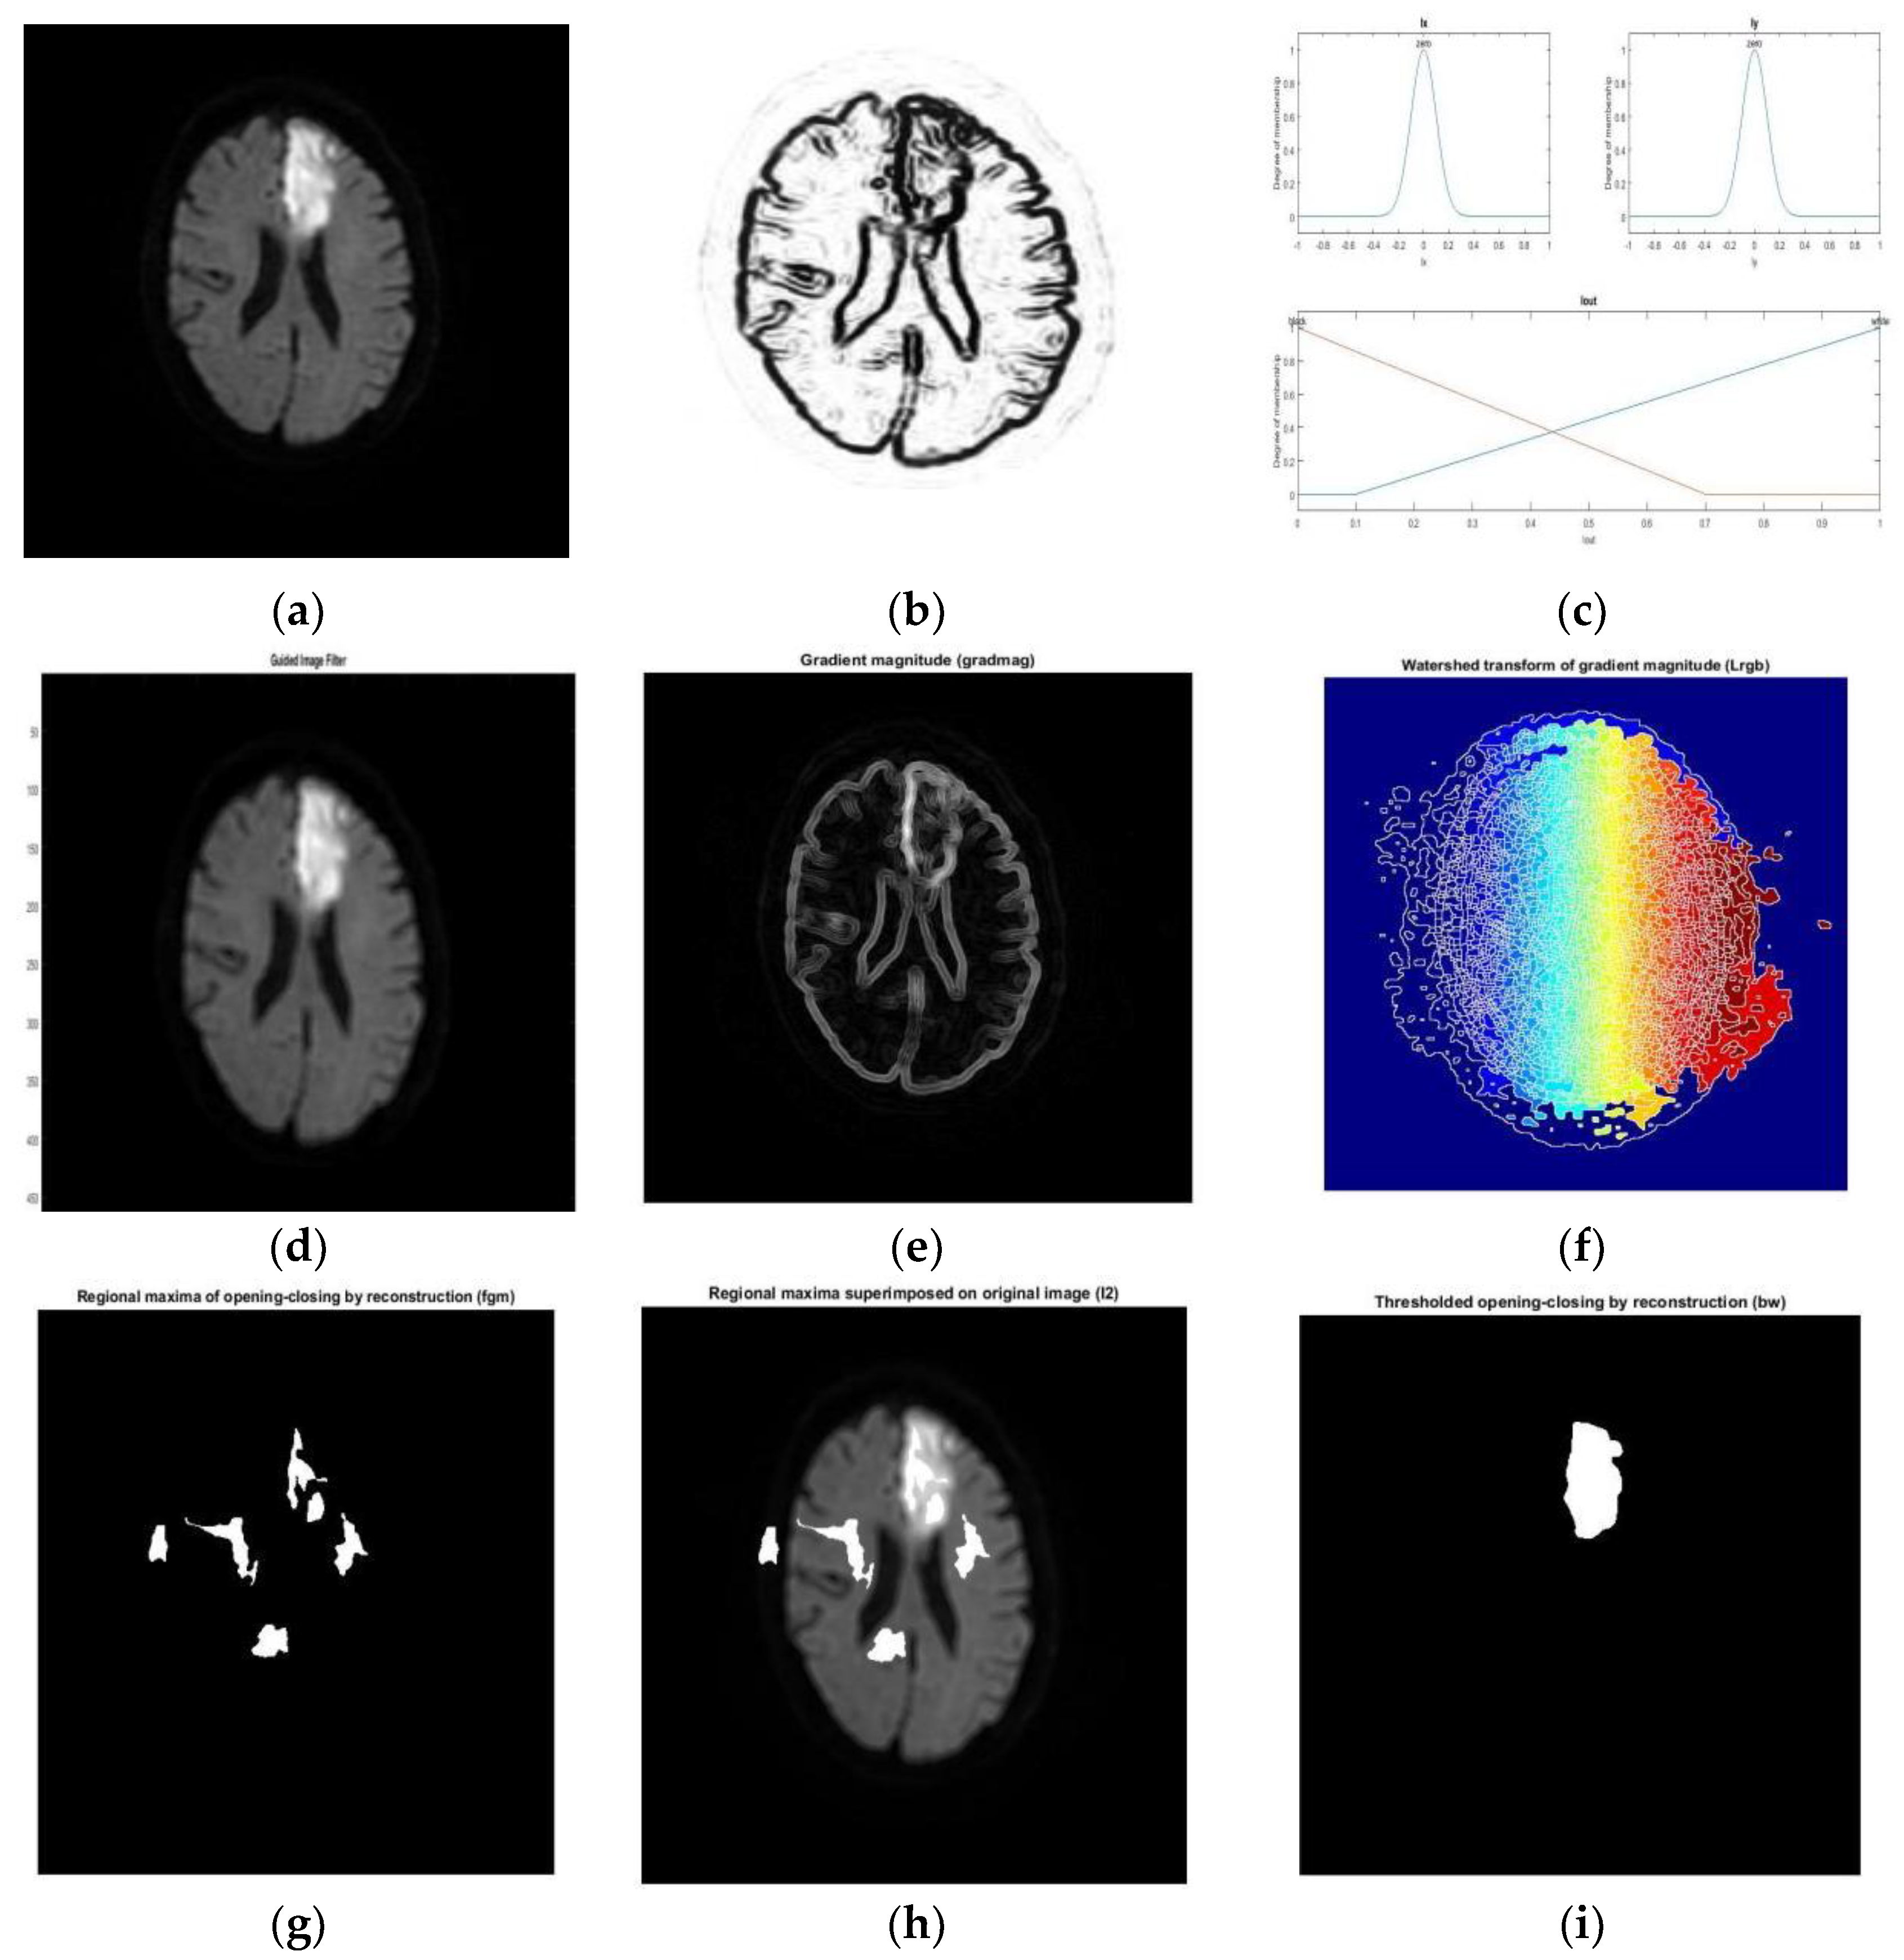

- Subudhi, A.; Jena, S.; Sabut, S. Delineation of the ischemic stroke lesion based on watershed and relative fuzzy connectedness in brain MRI. Med Biol Eng Comput. 2018, 56, 795–807. [Google Scholar] [CrossRef]

- Liang, Y.; Fu, J. Watershed algorithm for medical image segmentation based on morphology and total variation model. Int. J. Pattern Recognit. Artif. Intell. 2019, 33, 1954019. [Google Scholar] [CrossRef]